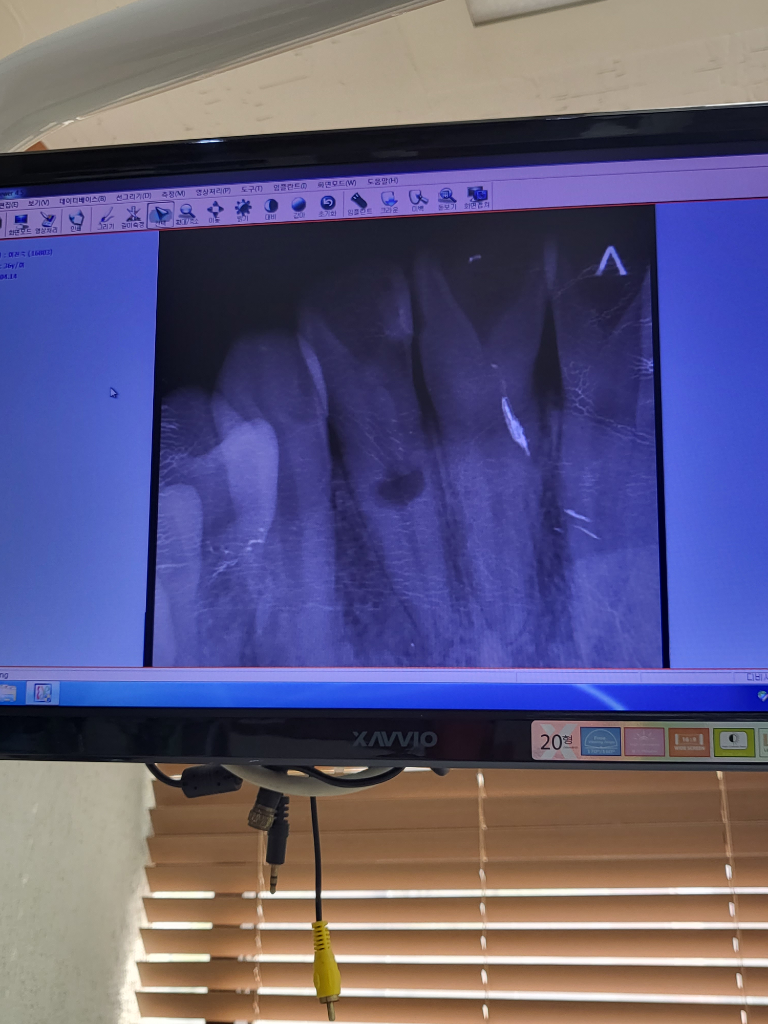

치아 내흡수 꼭발치해야할까요?

치통이 있어 치과를갔는데 치료방법이 없다하시네요 유지하다가 심해지면 발치후 임플란트하라고하는데 신경치료라던지 다른 방법으로 발치없이 치료할수없나요? 뼈가녹아버렸다고하는데 앞니이고 젊은나이인데 발치하기가 ㅠㅠ 답변좀남겨주세요.

• 1번 째 사진

지금 치통이 있으면 일단 신경치료 후 쓰는데 까지 쓰시면 됩니다. 내흡수 진행이 현상태에서 멈출 수도 있습니다.

치아 내흡수의 경우에는 치료 시도를 할 수 있습니다. 하지만 치료를 하더라도 치아 내흡수가 멈추지 않을 수 있고 신경치료 자체도 매우 까다로울 수 있습니다. 이러한 경우로 대학병원에서 치료를 시도하나 발치까지 생각하고 치료해야 하며 치료 이후 예후도 좋지 않은 편에 속합니다.

내흡수인 경우에는 대학병원의 보존과에서 진료를 받아보시면 최대한 살릴 방법을 시도해보실 겁니다.

치아의 내흡수가 발생한거 같습니다. 이럴경우 치아를 살려보고 싶다면 대학병원 보존과를 한번 가셔서 상담을 받아보세요. 일반 치과에서는 치료하기가 어려울것같습니다.

내흡수의 경우 발치 후 임플란트를 하기 전에

치료 횟수가 많고 예후는 좋지 않지만 신경치료를 시행해볼 수 있습니다

내흡수의 정도가 심하거나 치아에 남은 치질의 양(치아의 양)이 적으면 시행 불가능하므로 상담 해보시는 것이 좋습니다